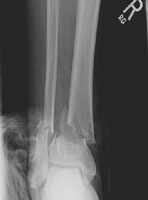

- Click on the image for a larger versionBAP radiograph of the tibia and fibula in a different patient. This demonstrates comminuted and mildly displaced fractures of the distal fibula and tibia.